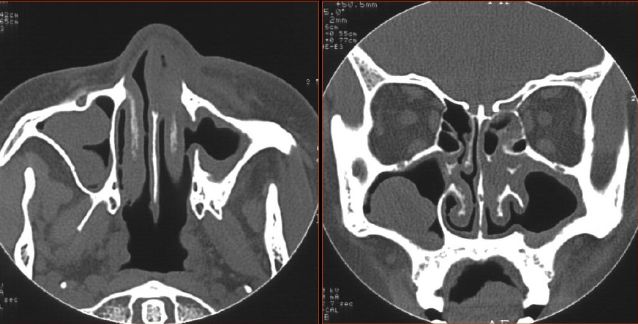

CT筛窦炎分型

1.蜂窝型:蜂房密集数量多,骨间隔菲薄

2.空泡型:蜂房少,融合成较大空泡,间隔较薄

3.骨质增生型:蜂房多少不一,骨间隔明显増厚,

部分间隔过度增生,蜂房融合闭锁

鼻窦骨壁增生

长期慢性炎症刺激

● 儿童期致鼻窦发育不良和窦腔狭小

● 骨炎的范围与感染的次数和病史的长短有关

● 分为硬化和肥厚

● 硬化是骨的细密化,多见于蝶窦和上颌窦

● 肥厚是骨壁的增厚一般向中心性

鼻窦炎—骨质改变

鼻窦炎—骨质增生